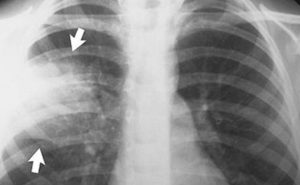

Рентген снимок атипичной пневмонии

Атипичная пневмония — собирательный термин, включающий инфекционно-воспалительные поражения тканей лёгких. Причинами являются нехарактерные возбудители — микоплазма, хламидия, легионелла, вирусы. Воспаление лёгких протекает с повышением температуры, одышкой, общим недомоганием.

Диагностировать патологический процесс можно при помощи рентгена. Так, для микоплазменной формы характерна неоднородная инфильтрация лёгочной ткани, она может определяться слабо или быть среднеинтенсивной.

При легионеллезной, на снимке видно уплотнения (инфильтраты) округлой формы, локализующиеся на поверхности одной доли лёгкого. В ряде случаев наблюдается слияние инфильтратов. У 25% пациентов одновременно с пневмонией определяется плеврит, с незначительным скоплением секрета в плевральной полости.

Правосторонняя бронхо- пневмония

Практически невозможно отличить пневмонию Legionella от других, основываясь на таком методе обследования. Присутствие легионеллы или хламидии подтверждается серологическим анализом крови.

Отдельное внимание стоит уделить воспалению неинфекционной этиологии. Одна из таких форм — инфаркт-пневмония, развивающаяся на фоне тромба, попавшего из лёгочной артерии в лёгкое. На рентгеновском изображении выступает как очаговое поражение с относительно чётким контуром.